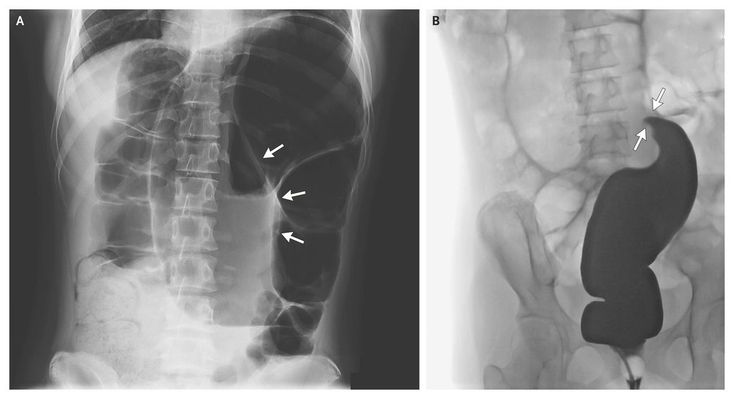

A 12-year-old girl presented with a 1-week history of constipation with one episode of vomiting. Initially, she had generalized abdominal pain. On admission, she reported having intermittent bilateral loin pain. She had no history of preexisting gastrointestinal disturbances. On physical examination, the abdomen was distended but soft with an empty rectum. The supine abdominal radiograph (Panel A) showed a large bowel dilatation, called the coffee-bean sign, with a cleft in the center (arrows) representing torsion of the sigmoid mesentery. Insertion of a rectal tube released a large volume of gas and a small amount of mucus. The contrast enema radiograph (Panel B) identified the bird's beak–like abrupt transition (arrows) at the level of the twist in the sigmoid lumen, confirming the volvulus. On laparotomy, a redundant segment of sigmoid colon measuring 45 cm in length and 15 cm at its widest diameter was resected. The patient's postoperative recovery was unremarkable. Sigmoid volvulus is an important cause of colon obstruction in adults but is rare in healthy children.